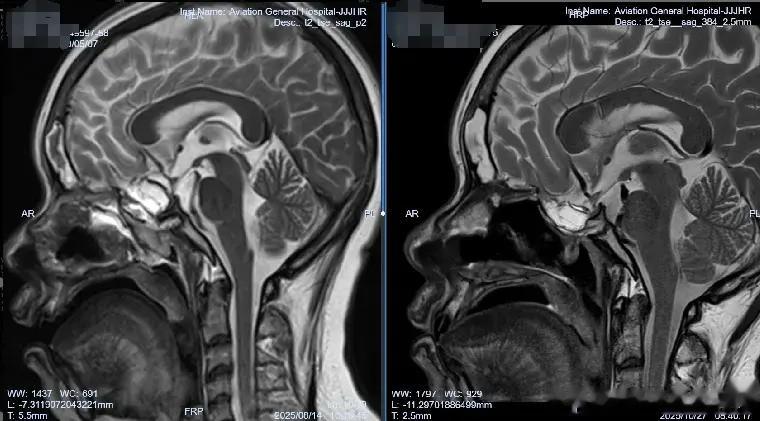

肖庆主任决定采取分阶段治疗策略:首先在2025年8月13日进行“腰大池置管引流”,建立初步引流通道;随后在8月21日实施“脑室腹壁外引流术”,建立持续引流通道。“精准的脑脊液管理是真菌性颅内感染治疗的关键。”肖主任强调,“我们不仅要控制感染,更要通过精细的引流调节,维持正常的颅内环境,为大脑恢复创造最佳条件。”

当引流管夹闭一周后,李女士没有出现任何不适,医疗团队知道,他们的治疗策略奏效了。2025年10月28日,肖庆主任为李女士成功结扎了引流管。那一刻,病房里洋溢着久违的轻松气氛。

肖庆主任表示,这个病例的成功得益于“个体化的脑脊液管理策略”与“精准的抗真菌治疗”的完美结合。“真菌性颅内感染治疗的最大挑战在于,它容易导致脑室系统粘连,进而形成脑积水。而通过精准的脑脊液外引流管理,我们不仅控制了颅内压力,还直接改善了药物分布,防止了并发症的发生。”